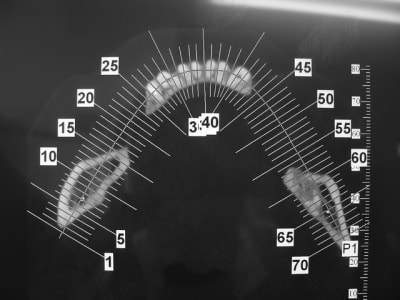

Patiente agée d'une trentaine d'année. En bouche la crête osseuse est inapparente et absence de gencive attachée.

Dans les secteur d'emmergence du nerf mandibulaire la palpation est douloureuse.

coupe_secteur_3_akuiru.jpg

pano_origine_nwhu2w.jpg

coupe_sect_4_c0hkw3.jpg

sinon secteur 3 y a peut être moyen dans certaines zones de travailler avec l'expansion...mais pas facile comme cas...surtout si la demande esthétique est +++

1. 2 séances d ostéotension

2. Epaississement vestibulaire en zone molaire nanobone prfd jason

3. pose de 2 cylindres enfouis en 34 44

4. pose de monodisk en 36 37 46 47 enfouis bloqués par vis ostéosynthèse

Bien vu! Je ne connaissais pas. C'est le même cas. J'aurai bien tenté mais ce qui "m'inquiète", c'est l'emmergence du mandibulaire. Sur le modèle du site je ne le vois pas; sur mon cas il serait juste au niveau du premier bloc et je me pose la question du surplomb ou de "l'irritation" possible.

Nous avons traité un cas comme ça avec D57,(secteur 3) os D1, manque de largeur résultat (de mémoire je n'ai pas les photos ici) 2 implants en même temps que l'expansion (34/37) et la suite 3 mois après le déplacement des volets vestibulaires, (bloqués sans vis) mais protégés par un bridge provisoire.

En conclusion, ce n'est pas un cas ou je ferais une greffe même pré ajustée (résultats en Décembre Pluton), mais une expansion sans doute avec déplacement/fracture du volet vestibulaire car os D1, mais si ça ce passe bien simple bone splitting et pose des implants dans la séance.